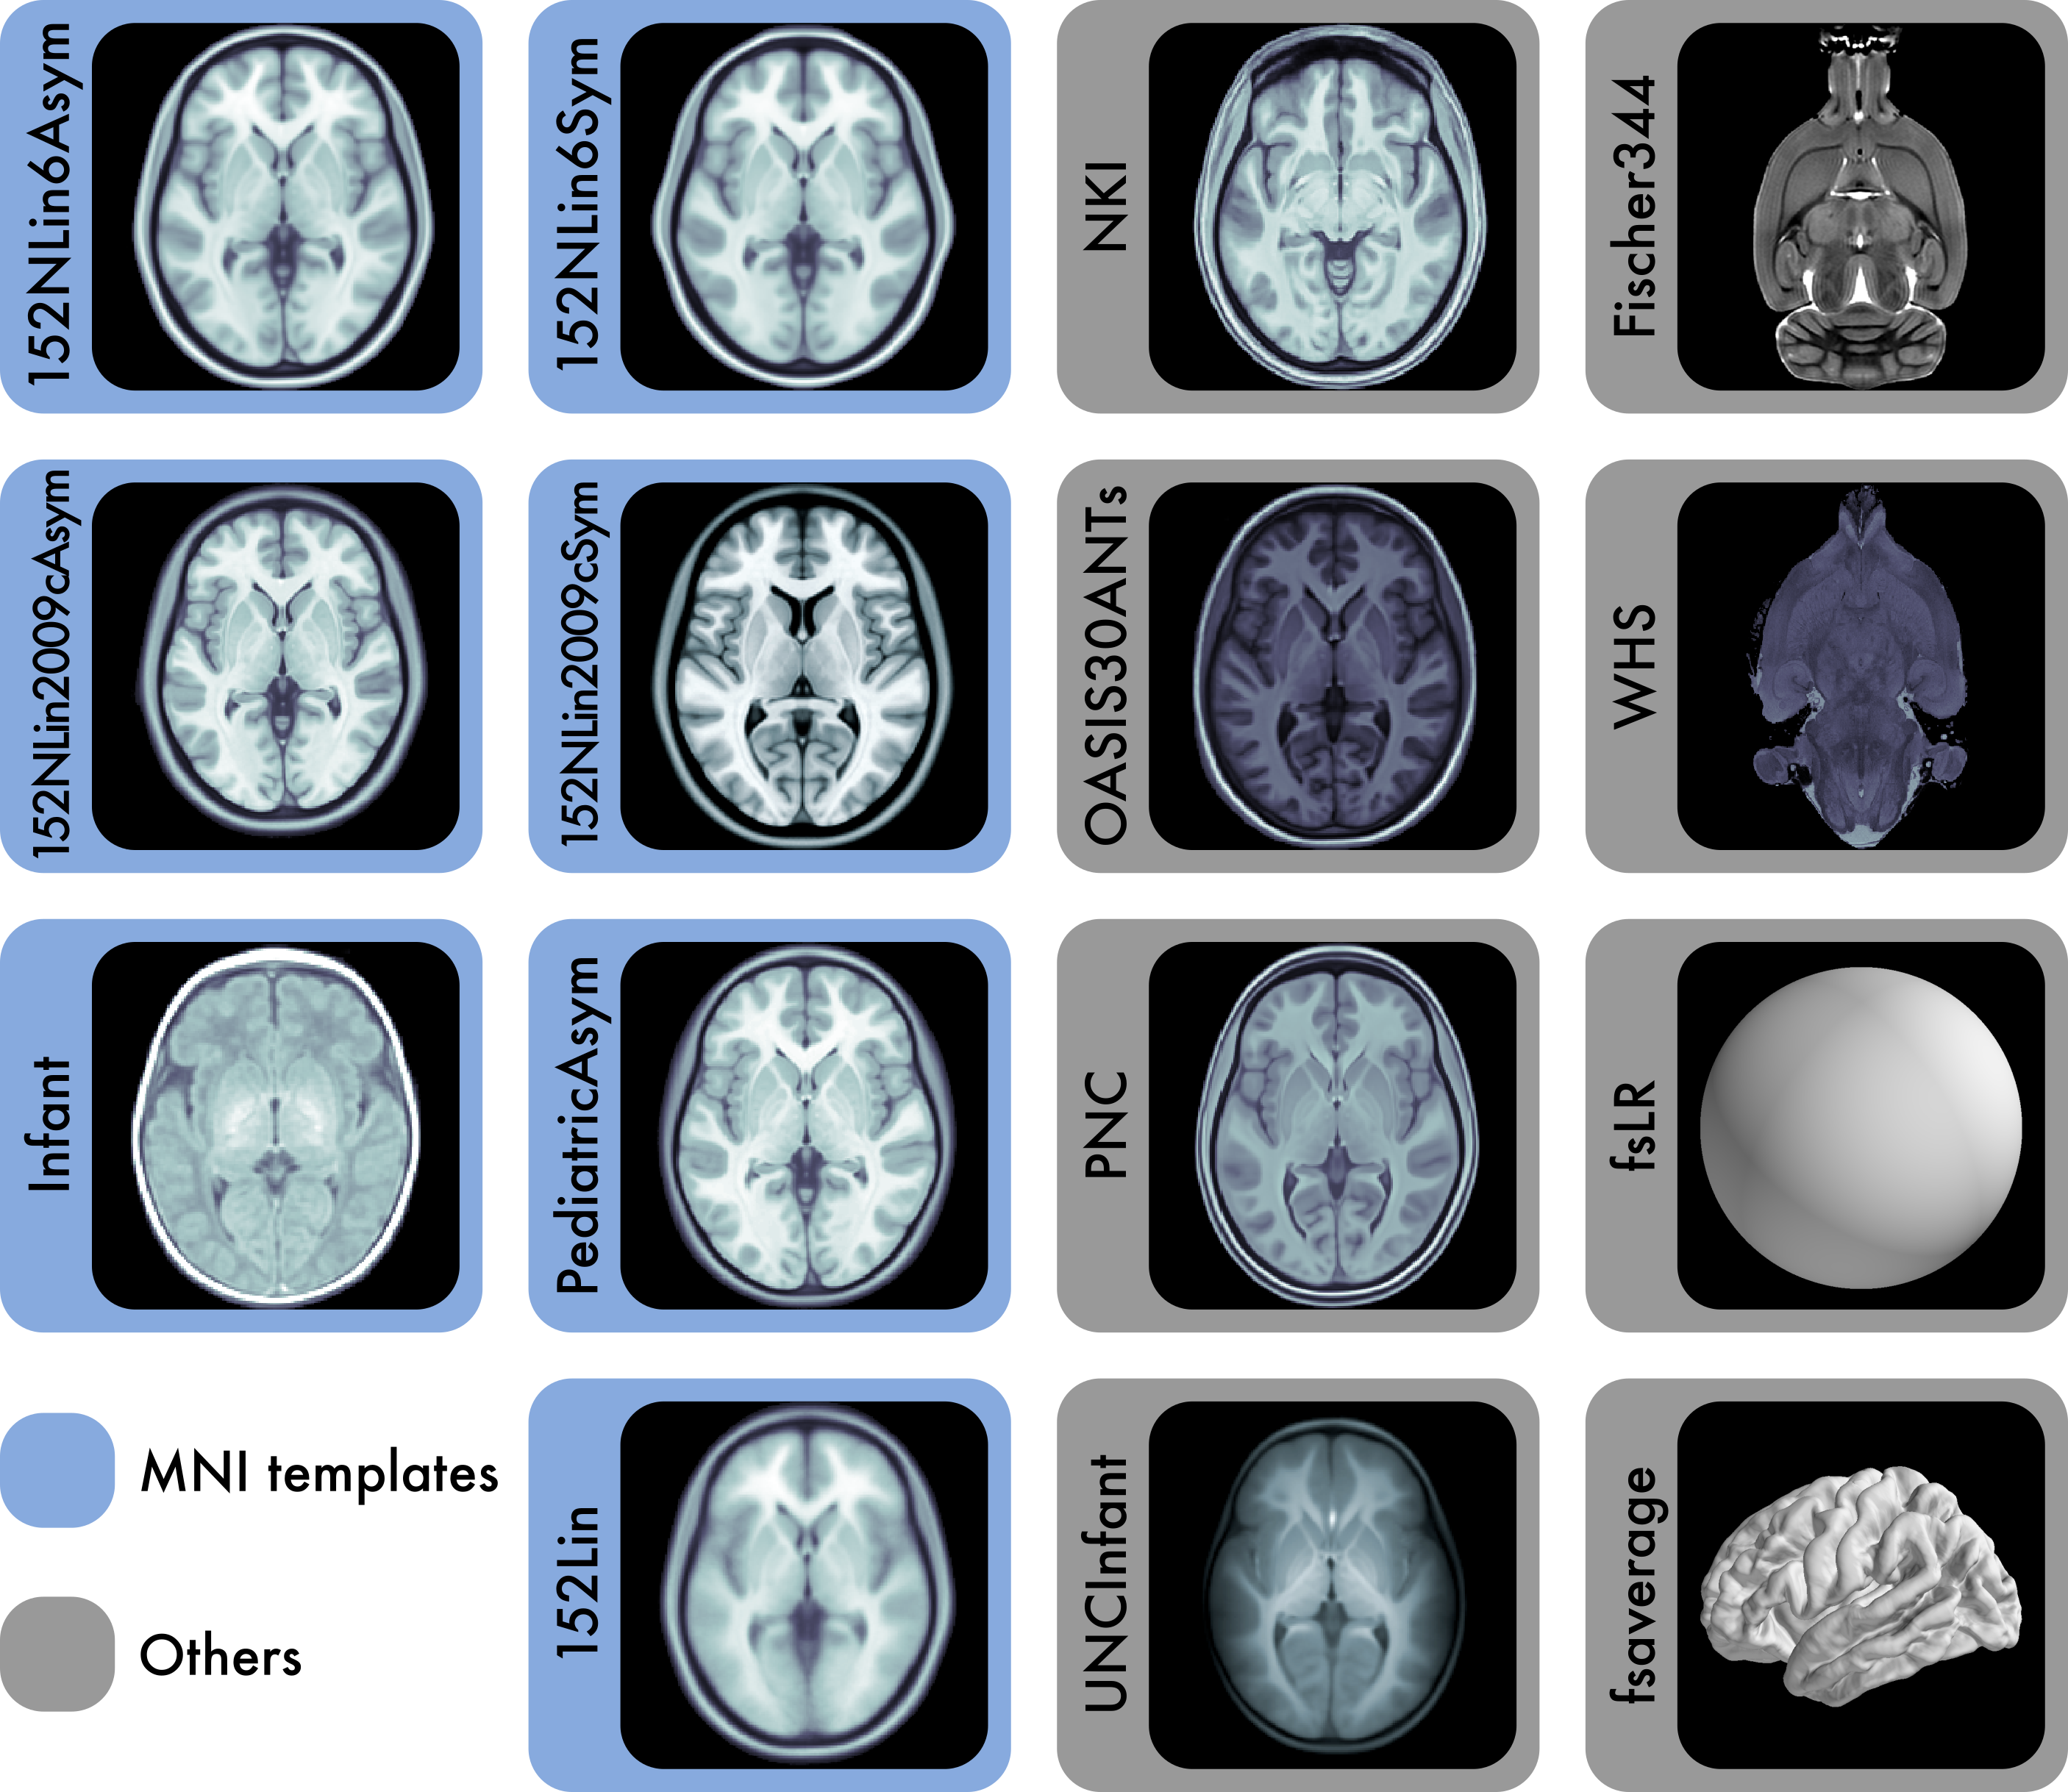

FAIR-sharing of multi-scale, multi-species brain models

About

TF templates